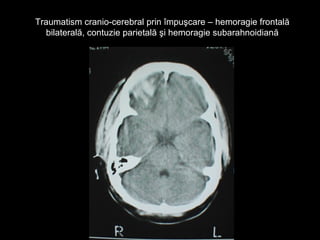

Traumatism cranio-cerebral prin împuşcare – hemoragie frontalăTraumatism cranio-cerebral prin împuşcare – hemoragie frontală

bilaterală, contuzie parietală şi hemoragie subarahnoidianăbilaterală, contuzie parietală şi hemoragie subarahnoidiană